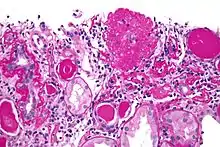

| Light micrograph of focal segmental glomerulosclerosis, hilar variant. Kidney biopsy. PAS stain. | |

The individual components of the name refer to the appearance of the kidney tissue on biopsy: focal—only some of the glomeruli are involved (as opposed to diffuse), segmental—only part of each glomerulus is involved (as opposed to global),[19] glomerulosclerosis—refers to scarring of the glomerulus (a part of the nephron (the functional unit of the kidney)). The glomerulosclerosis is usually indicated by heavy PAS staining and findings of immunoglobulin M (IgM) and C3-convertase (C3) in the sclerotic segment.[20]